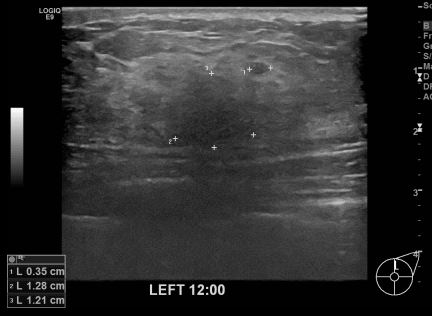

아산유외과개원후 658번째 유방암진단

상기환자 외부검사상 이상소견으로 내원하신 50대여성으로 좌측에 의심스러운혹 조직검사시행해 유방암 진단되었습니다.